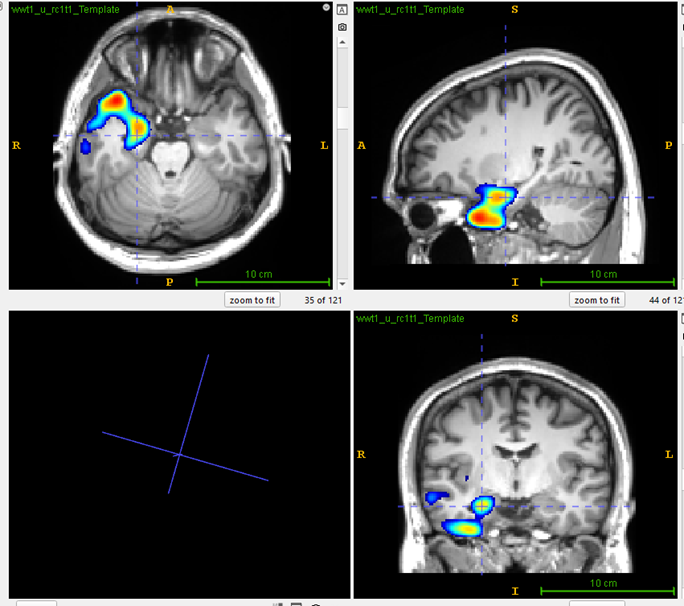

MRI Scan

Visual analysis: PET scan of a patient with drug-resistant temporal lobe epilepsy showed bilateral temporal lobe hypometabolism.

PASCOM: Focal hypometabolism was localized to right hippocampus and temporal pole cortex.